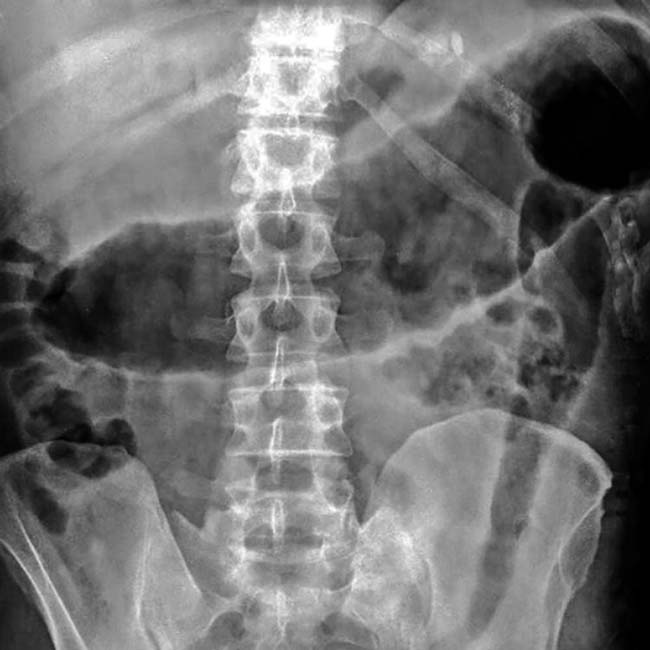

Диагностика вздутия толстой кишки: рентгеновские снимки и описание